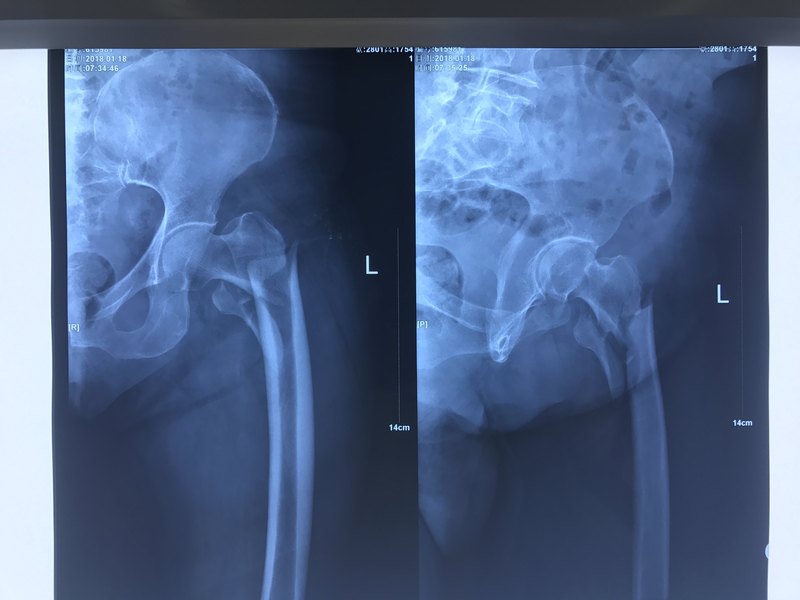

股骨轉(zhuǎn)子間骨折被稱(chēng)為人生最后一次骨折,最后一次骨折,說(shuō)的是以后就不會(huì)再骨折了嗎?顯然不是,這“最后一次”,是因?yàn)楹芏喙晒墙斯钦鄣睦先?,在骨折后因?yàn)楦鞣N原因去世,連再次骨折的機(jī)會(huì)都沒(méi)有了。 為什么?先來(lái)看看這根股骨吧。說(shuō)股骨可能一部分人不知道是哪一根,其實(shí)就是大腿骨,最粗壯的骨骼,沒(méi)有它的支撐,我們連站都站不起來(lái)。股骨近端,就是髖部的那一端,這個(gè)部位在我們年輕時(shí)是十分強(qiáng)大的,摔一下子拍拍屁股站起來(lái)就走,很少有骨折的,但上年紀(jì)后就不行了,保護(hù)它的強(qiáng)大肌肉逐漸萎縮,骨折自身也不再爭(zhēng)氣,骨質(zhì)變得疏松,尤其是絕經(jīng)后的女性,骨量流失非??欤嗳醯墓穷^像塊餅干,逢到踩空摔倒就很可能骨折了。 骨折,做個(gè)手術(shù)接上不就行了?但對(duì)于股骨近端骨折的老年人,事情就沒(méi)這么簡(jiǎn)單了。 首次,得符合手術(shù)條件。年齡、身體狀況、有沒(méi)有高血壓、糖尿病等基礎(chǔ)病,再加上手術(shù)中出血,失血量大是否可以承受,各種臟器都在走下坡路的人并發(fā)癥風(fēng)險(xiǎn)有多大,是否能承受術(shù)后抗凝藥物的使用等,這些都是必要的條件,所以并不是每個(gè)人都能順利接受手術(shù)治療。 不手術(shù)保守治療是不是也可以?可以,但肺部感染的威脅會(huì)一直伴隨著臥床的老人。長(zhǎng)期臥床的人,肺部分泌物排出就變得很困難,長(zhǎng)時(shí)間淤積于中小氣管中,成為細(xì)菌“培養(yǎng)基”,極易誘發(fā)肺部感染造成墜積性肺炎,而這種肺炎對(duì)臥床者來(lái)說(shuō)可能是致命的。 其次就是褥瘡,護(hù)理稍有不勤,沒(méi)有給臥床的人常翻身就可能壓出褥瘡。實(shí)習(xí)時(shí),曾接過(guò)一位老人,褥瘡深得見(jiàn)了骨頭,最后老人最終因感染去世了 還有一個(gè)看不見(jiàn)的殺手,因長(zhǎng)期臥床血循緩慢等引發(fā)的下肢深靜脈血栓,血栓脫落后游到肺部堵住血管造成的致命性肺栓塞。 有國(guó)外統(tǒng)計(jì)顯示,老年人發(fā)生股骨近端骨折,一年后的生存率只有約50%,這也是被稱(chēng)為“人生最后一次骨折”的原因。 預(yù)防這種可怕的骨折,生活方式尤其重要。 首先,要改變長(zhǎng)期吸煙、大量飲酒、嗜飲濃茶、缺乏運(yùn)動(dòng)的生活習(xí)慣。 其次,很多人飲食中鈣含量很低,尤其是女性,很容易在更年期后出現(xiàn)骨質(zhì)疏松,埋下骨折的隱患,從30歲之后就要有意識(shí)地喝牛奶、吃油菜、芥藍(lán)、蝦皮、西蘭花等含鈣量高的食物